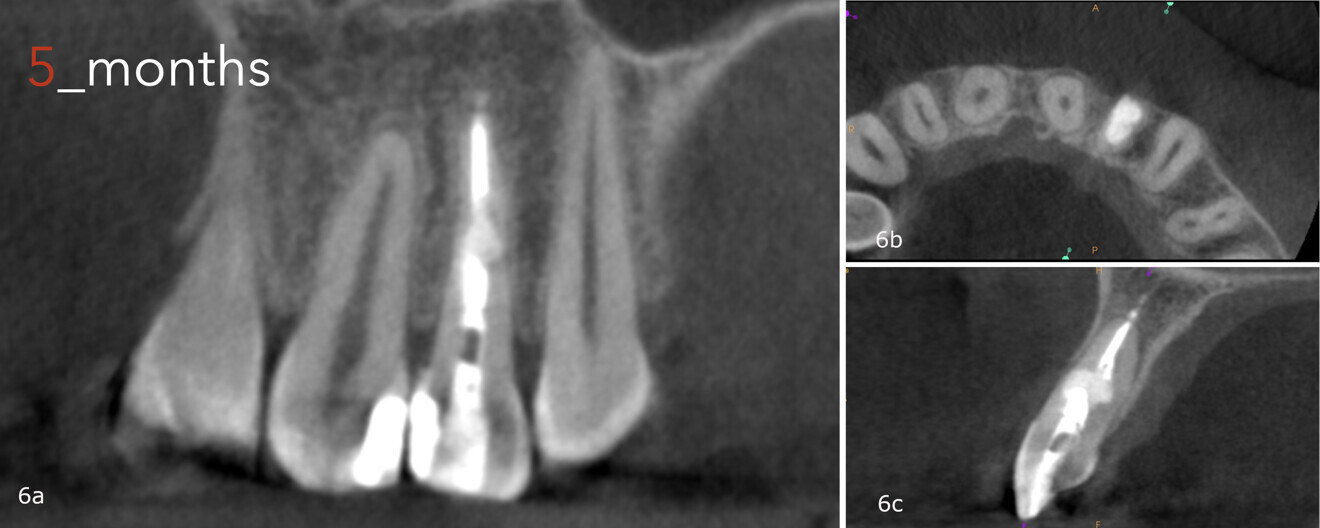

Recall appointments were performed after five and six months (Fig. 5). The bone healing was complete after five months (Figs. 6a-c), and after 30 months, there were no signs of the bone defect, fracture or any other abnormalities (Figs. 7a & b).

Figs. 6a–c: CBCT scan taken five months after the treatment, showing the healed lesion.